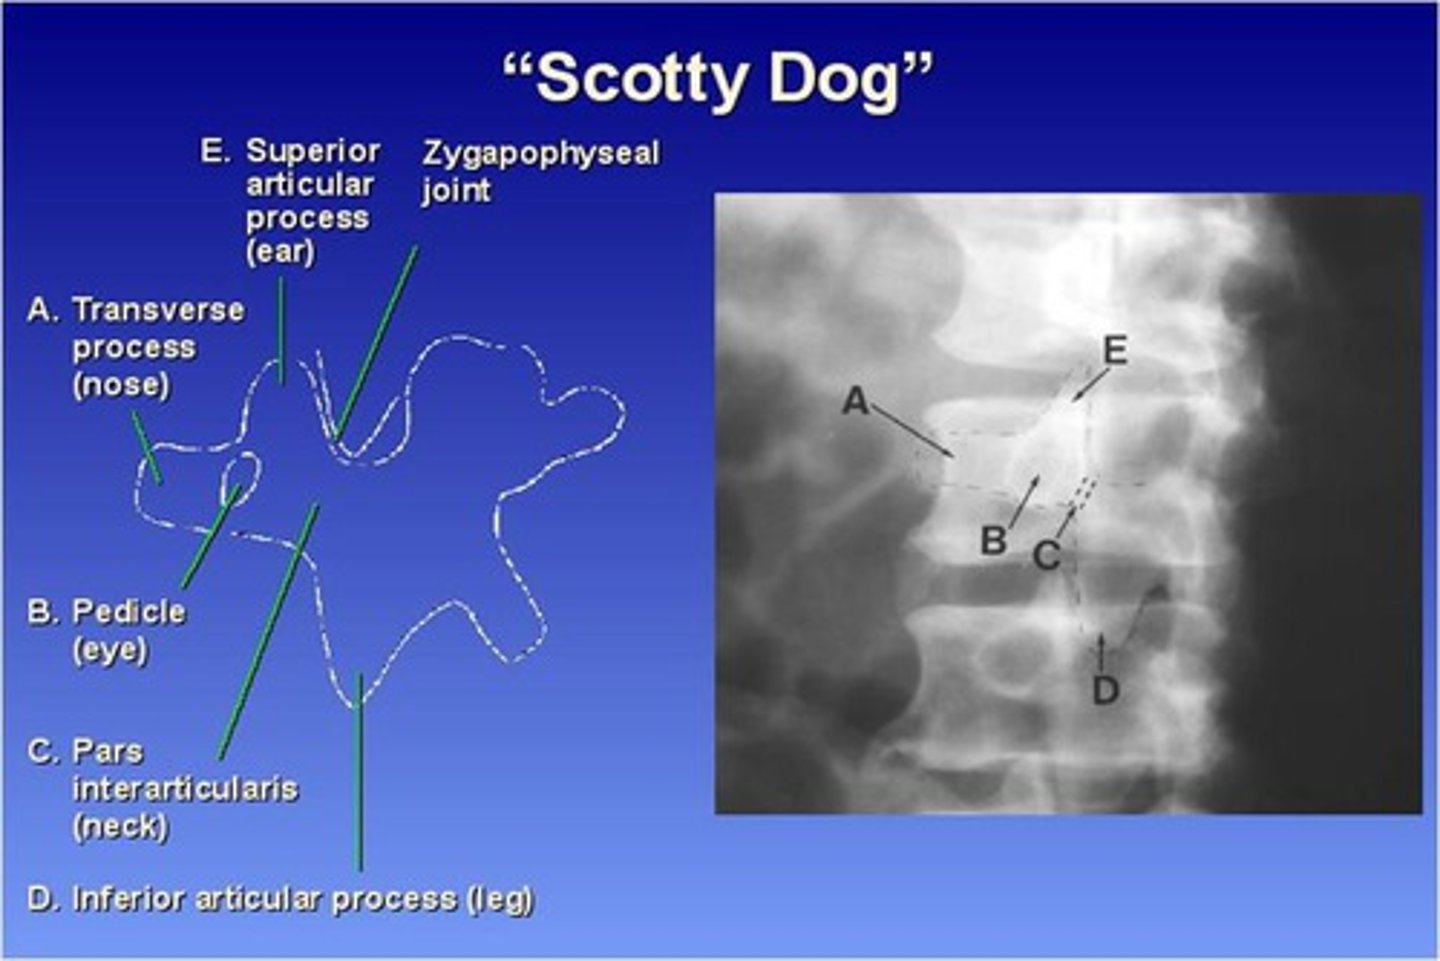

The Lumbar zygapophyseal joints are ONLY demonstrated on what view?

45 degree obliques (will see "scotty dog")

What part of the lumbar spine makes up the "nose" of the "scotty dog"?

transverse process

What part of the lumbar spine makes up the "eye" of the "scotty dog"?

pedicle

What part of the lumbar spine makes up the "neck" of the "scotty dog"?

pars interarticularis

What is the pars interarticularis?

portion of each lamina between the superior and inferior articular processes

What part of the lumbar spine makes up the "leg" of the "scotty dog"?

inferior articular process

What part of the lumbar spine makes up the "ear" of the "scotty dog"?

superior articular process